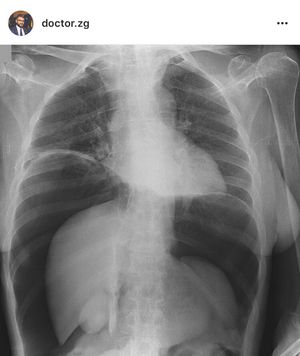

Dx?

Pneumoperitoneum